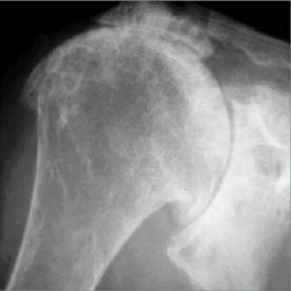

De reversed prothese of omgekeerde schouderprothese is een oplossing voor hen die een versleten schouder hebben waarbij de rotator cuff heel zwaar en onomkeerbaar beschadigd is. Daardoor beweegt de schouder abnormaal in zijn gewricht en krijgt men secundair kraakbeen beschadiging.

Voor de patiënt heeft dit tot gevolg dat de schouder pijn geeft bij beweging en tijdens de nacht.

Een belangrijker gegeven is het krachtsverlies die er optreedt bij heffen en gebruik, tot zelfs een onmogelijkheid om de arm in de hoogte te steken. Een pseudo verlamming.

Initieel wordt geprobeerd de pijn weg te krijgen met medicatie, inspuitingen en kinesitherapie. Het krachtsverlies blijft er altijd bestaan vermits er geen nieuwe aanhechting komt van de verloren pezen.